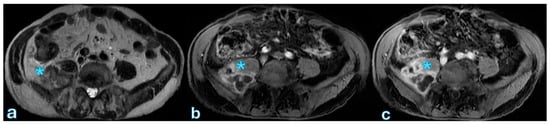

On contrast-enhanced imaging, splenic infarction is radiologically represented as a wedge-shaped, non-enhancing area, with its base along the splenic capsule and its tip pointing toward the splenic hilum (Figure 7).

Over time, these infarcts may completely resolve or result in progressive splenic atrophy due to fibrotic contraction of the infarcted tissue. Early radiologic identification of splenic infarction is essential to ensure appropriate clinical monitoring while avoiding unnecessary interventions in asymptomatic patients.

11. Peculiar Issue After Pancreaticoduodenectomy: Disease Recurrence

Local recurrence following curative-intent pancreatic cancer resection is common, typically occurring within two years postoperatively, with median survival significantly impacted by adjuvant therapy—ranging from 11 months with surgery alone to approximately 20 months when combined with chemotherapy [160]. Surveillance guidelines from the NCCN (v.2 2023) recommend clinical evaluation every 3–6 months for the first two years, including CA 19-9 monitoring and abdominal–pelvic CT imaging, although evidence supporting imaging frequency remains limited. Conversely, ESMO guidelines do not specify routine imaging protocols due to insufficient evidence on survival benefits [161]. Surveillance’s effectiveness in improving survival is controversial, with analyses like the SEER-Medicare database indicating no clear survival advantage. Nevertheless, early detection of isolated locoregional recurrence may permit re-resection, potentially enhancing survival outcomes. Recurrence patterns commonly involve local recurrence at surgical margins, particularly after pancreaticoduodenectomy, presenting as infiltrative soft tissue with perineural invasion and progressive vascular encasement, distinguishable from normal postoperative changes by serial imaging (Figure 8).

A baseline postoperative scan at 6–8 weeks aids in accurate longitudinal assessment. Distant metastases frequently involve the liver and peritoneum, with MRI, especially diffusion-weighted and hepatobiliary contrast-enhanced imaging, demonstrating superior sensitivity in identifying subtle hepatic lesions compared to CT (Figure 9).